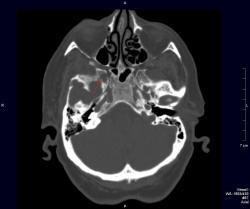

Женщина средних лет с клиникой невралгии тройничного нерва справа. На КТ были вывлены округлые очаги деструкции в костях основания черепа (средней черепной ямки).

Спасибо за ответ. Плазмоцитома действительно может быть где угодно, просто картина очагов при миеломной болезни наиболее характерна в плоских костях. Я собственно и спросила о миеломной болезни, поскольку очаги деструкции круглые, четкие, ровные, а про рак молочной железы Вы сразу не упомянули... Кстати, метастазы как раз рака молочной железы иногда имеют вид "пробойников"

Череп деформирован - аномалия развития + вероятно фиброзная дисплазия.

Нет, асимметрия за счет укладки. Череп обычный. У пациентки выраженный болевой синдром, из-за которого трудно было уложить ее ровно.